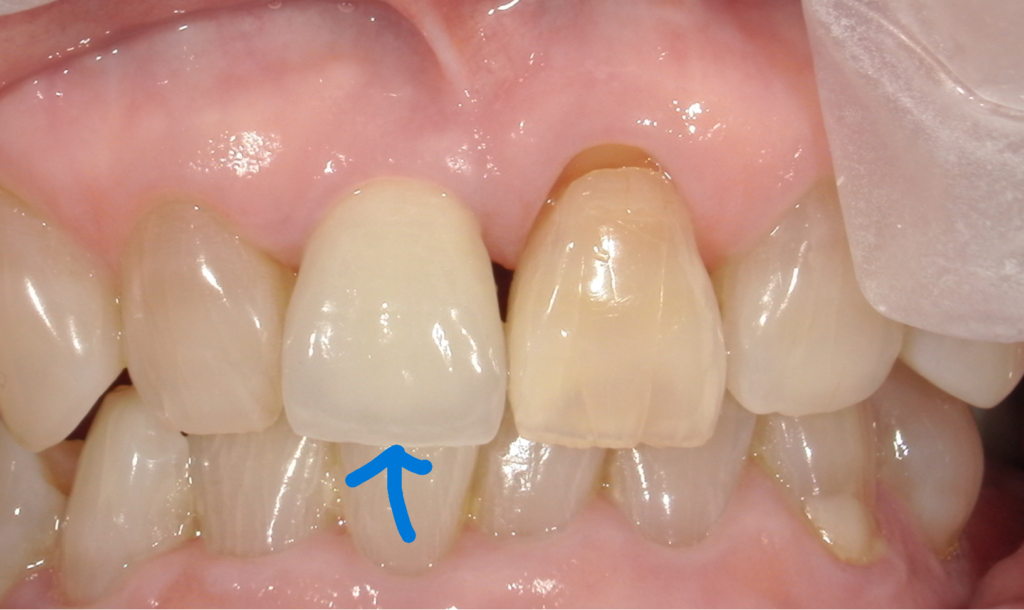

拡大してみますと、どうしても一般の方は歯の色の微妙な違いが気になるかもしれません。しかし私たちが見るところは青い〇 と緑の〇。ここら辺なのです。

根本のふくらみが自分の歯とインプラントとが何年たってもそんなに違わない。

実はこのケース、

ダメになった歯を抜歯する際に、歯の一部(健康な部分)を薄く残しているんですね。

つまりわざと歯のかけらをここに残してそのままインプラントしています。

ルートメンブレン法という技術ですね。

自分の歯の一部があれば、周囲組織はが吸収しないことを利用しています。

手技的にはとても難しく厄介なものです。

しかし、うまくいけば、このように何年経っても周りの自然な自分の歯と同じ、歯肉のふくらみを保てます。